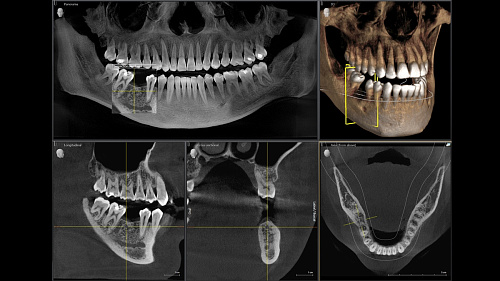

Диагностика последнего поколения, идеально решающая задачи рентгеновского обследования независимо от размеров клиники. Поля изображения зависят от определенной клинической картины, поэтому специалистам так удобно работать с ORTHOPHOS SL 3D. Данная установка делает объёмные картинки для одиночной реставрации в 3D качестве полностью всей челюсти такого размера, которого требуется.

Планирование одиночной реставрации, эндодонтические исследования и пр. – для этого специалист может выбрать объёмные варианты 8 х 8 см или 11 х 10 см, также предлагается объём 5 х 5,5 см. Снимки в HD-качестве, стандартные настройки или выбор объёма обследования в зависимости от диагноза — всё это врач получает в отличном качестве, а для пациента излучение в районе исследования минимально.